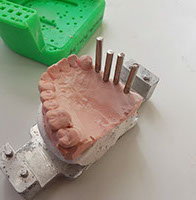

innovación dental

innovación dental